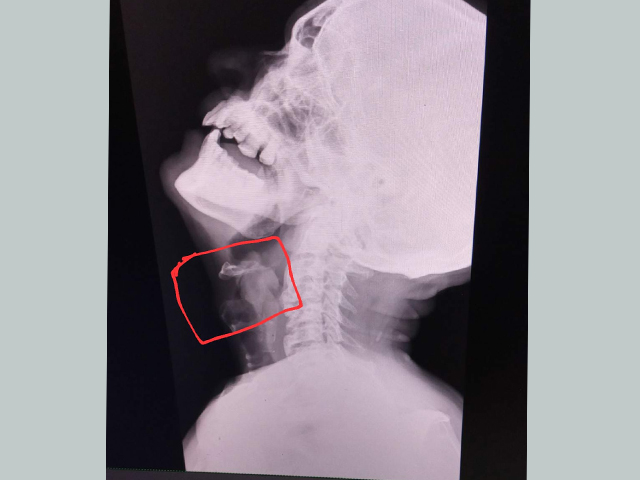

We are providing 24X7 emergency care services for Ear Nose Throat and Neck emergency like trauma with Ear / Nose Bleeding, cut throat injury, Acute airway obstruction with stridor, Foreign Bodies in Ear, Nose, Food passage and Airway.